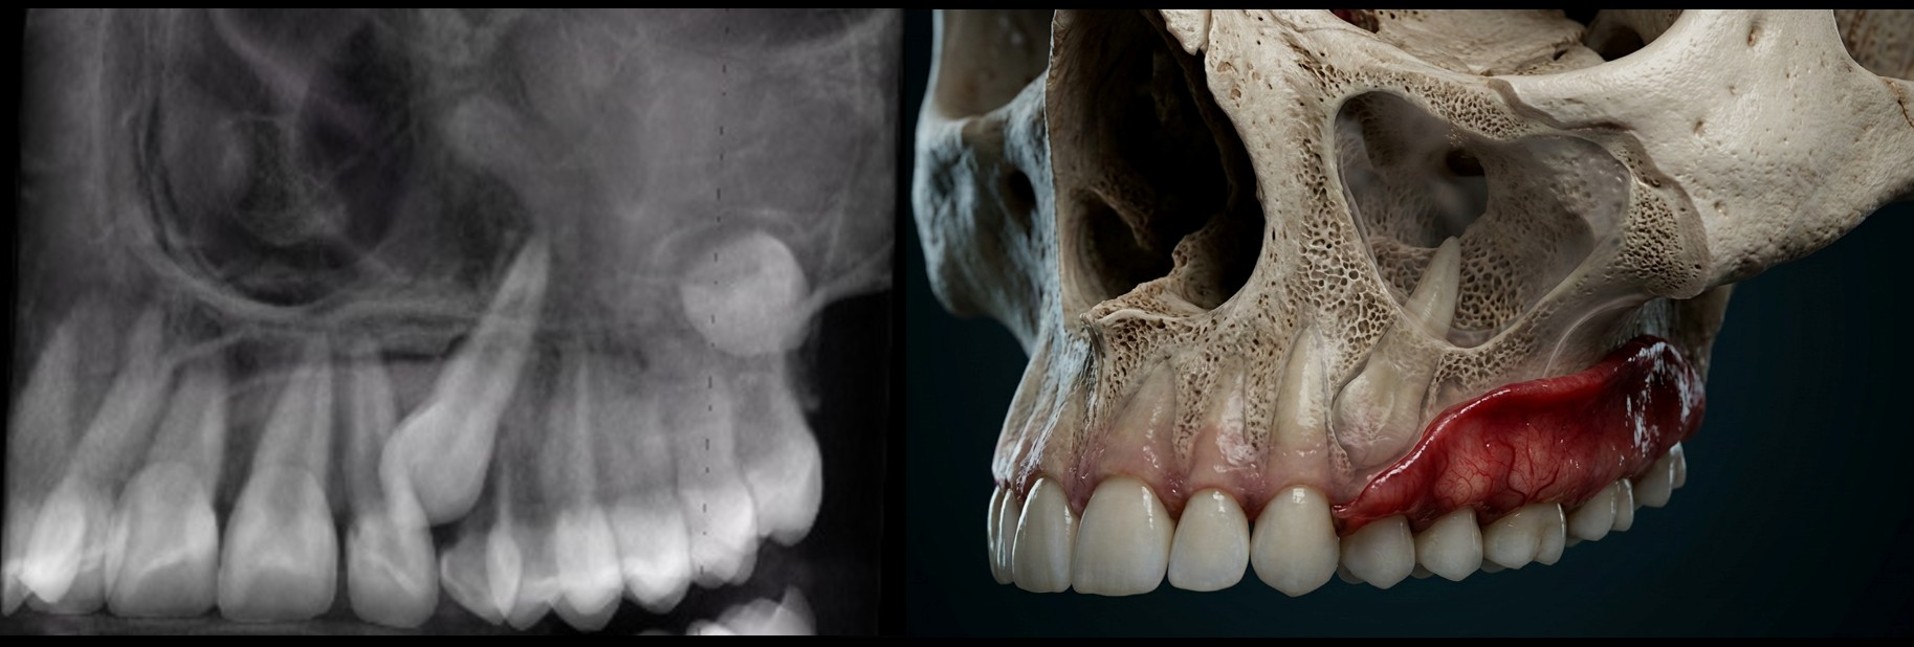

Hands-on training with AI tools to enhance and recolor CBCT data. Create hyper-realistic anatomical renderings using large language model software — images that educate patients and elevate your practice.

One of the most powerful skills you'll gain: using large language model software to transform raw CBCT data into stunning, clinically accurate anatomical renderings. These images revolutionize patient communication and case presentation.